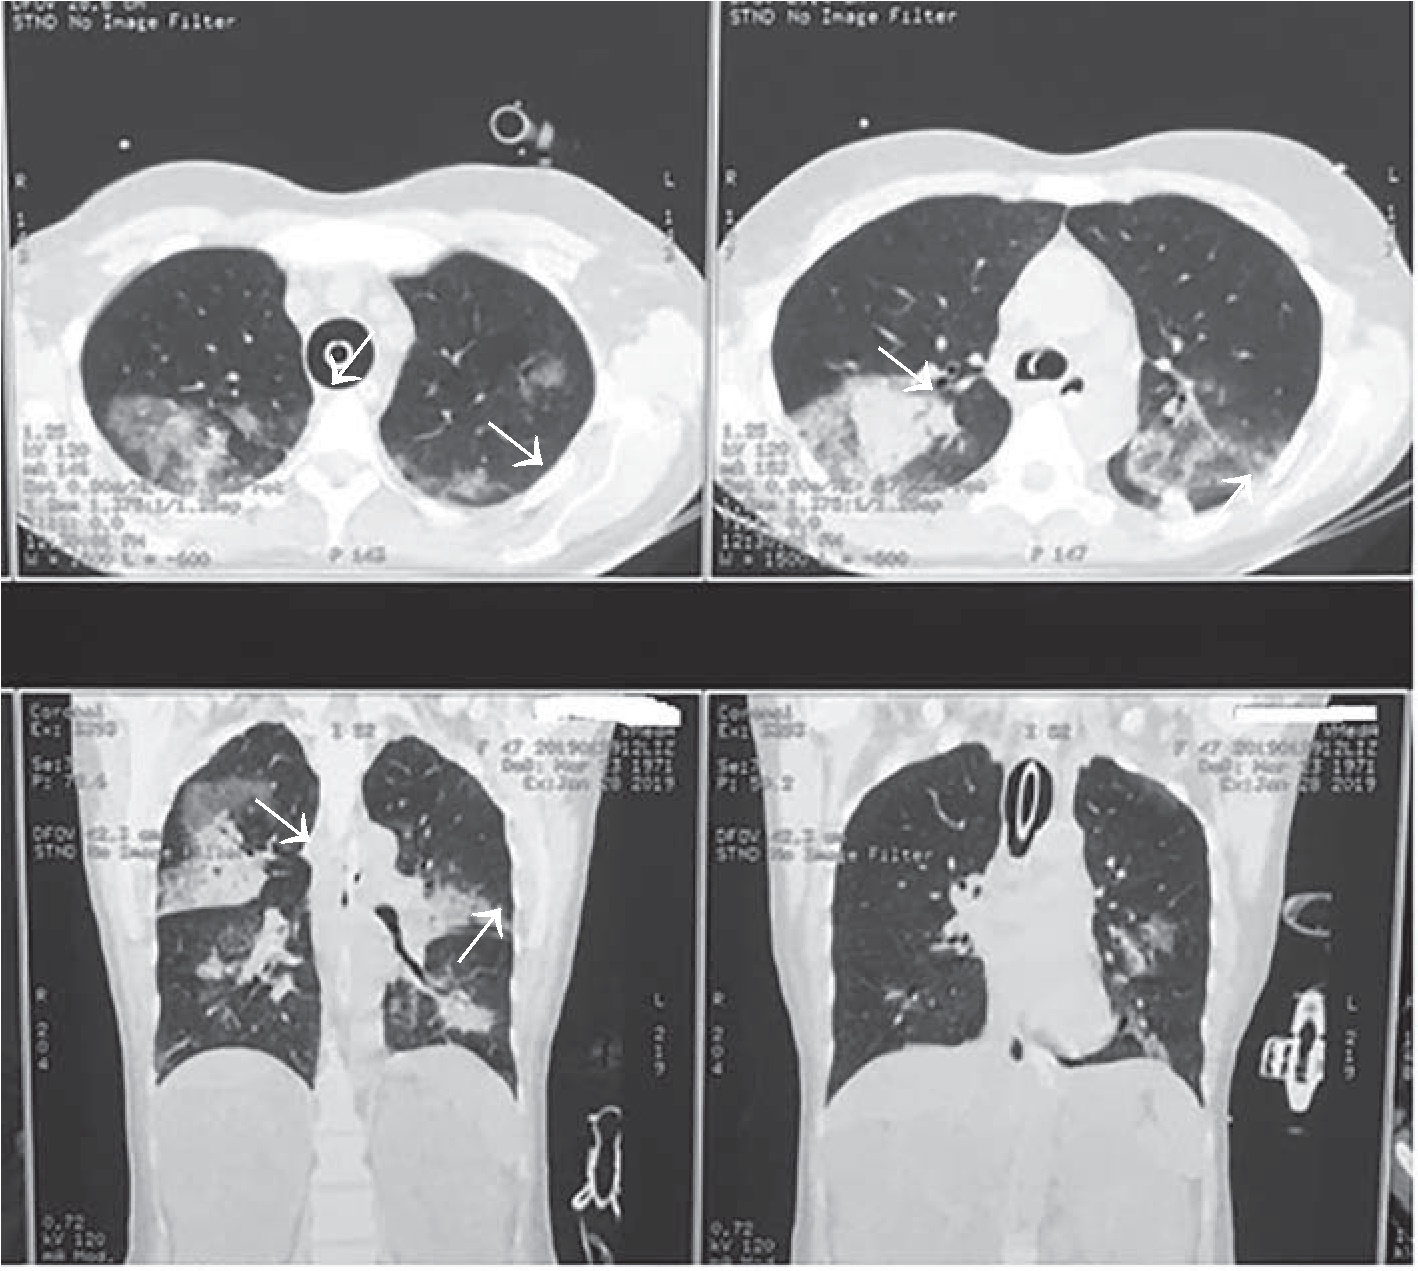

26.01.2019 г. для исключения патологии со стороны центральной нервной системы, уточнения причин угнетения сознания с развитием судорожного синдрома, исключения отека легких, аспирационного синдрома, а также исходя из наличия в анамнезе поликистоза почек пациентке была выполнена КТ головы (рис. 1), груди (рис. 2), живота (рис. 3), по результатам которой отмечалось минимальное субарахноидальное кровоизлияние в височной доле справа; имелись признаки аксиальной дислокации 1 – 2 степени. Объёмных образований, гематом в веществе головного мозга не выявлено. Пристеночное утолщение слизистой оболочки в лобной пазухе, клетках решетчатого лабиринта, обеих верхнечелюстных пазухах и основной пазухе слева с наличием в последней минимального уровня содержимого. Диффузная интерстициально- альвеолярная инфильтрация лёгочной ткани с обеих сторон с наличием небольшого количества жидкости в плевральных полостях, вероятно, как проявления отёка лёгких. В зоне сканирования поликистоз печени, почек.

Рис. 2. КТ легких. Визуализируется небольшое количество жидкости в плевральных полостях как проявление отёка лёгких

Повторно выполнены КТ груди, живота. Заключение: диффузная интерстициально-альвеолярная инфильтрация легочной ткани с обеих сторон, вероятно, как проявление отека легких, на фоне которого нельзя исключить наличие пневмонической инфильтрации в базальных отделах обоих легких. Жидкость в обеих плевральных полостях. Гепатомегалия. Множественные кисты печени. КТ-картина поликистоза почек. Жидкость в ложе желчного пузыря. В сравнении с исследованием от 26.01.2019 г. отмечается появление геморрагического содержимого в заднем роге левого бокового желудочка, в полости четвертого желудочка и цистерне четверохолмия, появление содержимого в правой половине основной пазухи, незначительное разрешение инфильтрации в верхних долях обоих легких и уплотнение инфильтрации в базальных отделах.